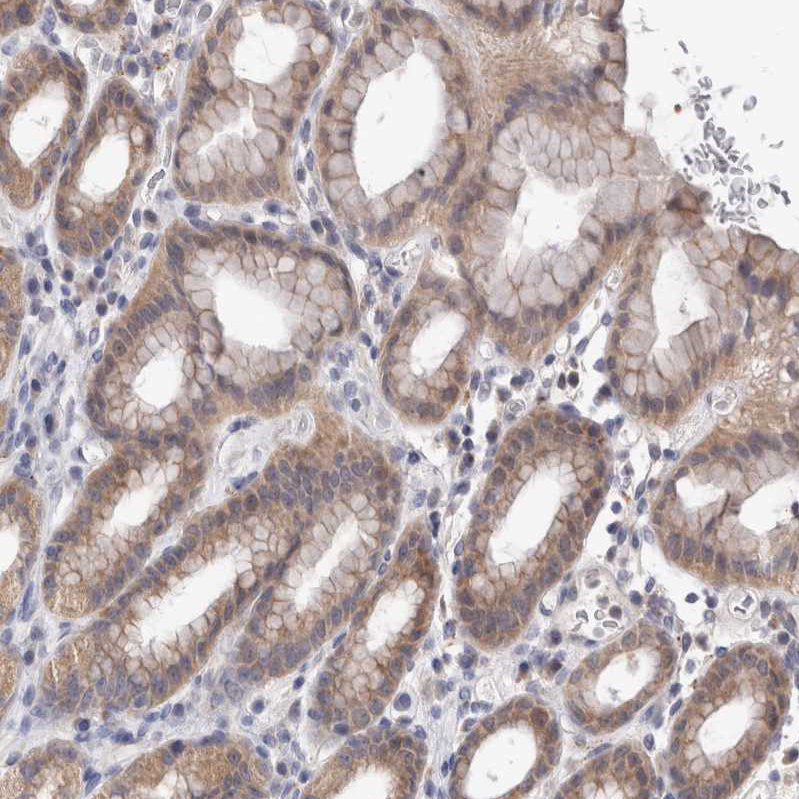

Immunohistochemical staining of human fallopian tube shows moderate cytoplasmic positivity in glandular cells.